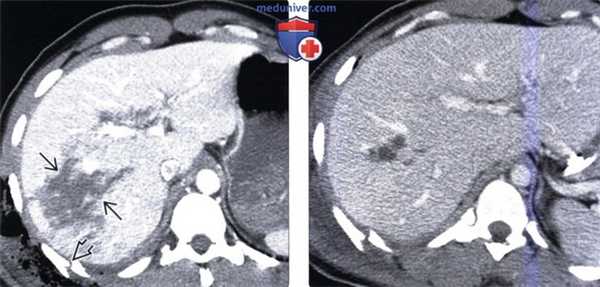

(Слева) На аксиальной КТ у женщины 33 лет определяется перелом ребра со смещением отломков, а также глубокий разрыв паренхимы печени. В подкожной клетчатке видны включения газа. Разрыв распространяется вплоть до крупных вен печени, однако признаков активной экстравазации не обнаруживается.

(Справа) На аксиальной КТ с контрастным усилением, выполненной десять дней спустя этой же пациентке, определяется разрешение гемоперитонеума и частичное заживление разрыва печени. Поскольку консервативное лечение эффективно для большей части пациентов с повреждением печени в результате тупой травмы, находящихся в стабильном состоянии, позволяющем выполнить КТ, часто удается обойтись без операции.